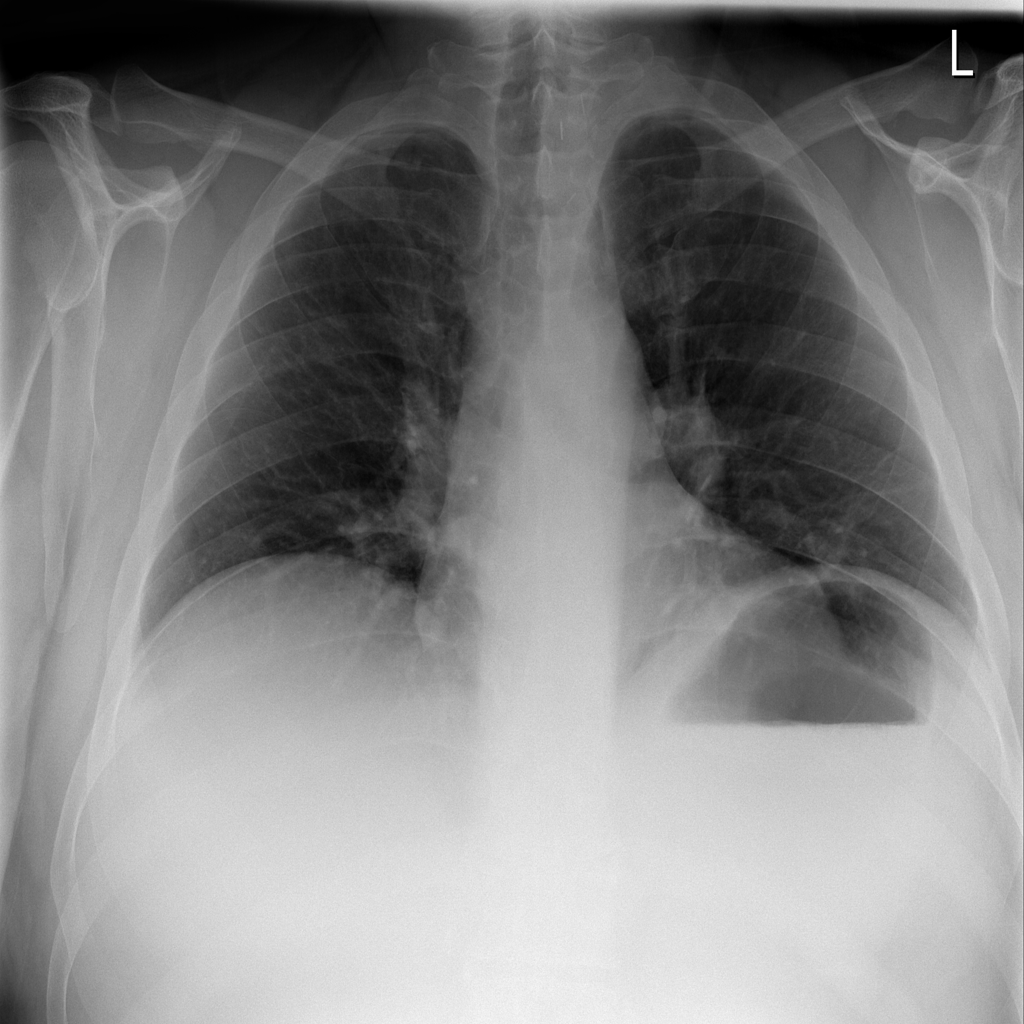

PAT-75D0 · IMG-001Pneumonia

PAT-75D0 · IMG-001

PA